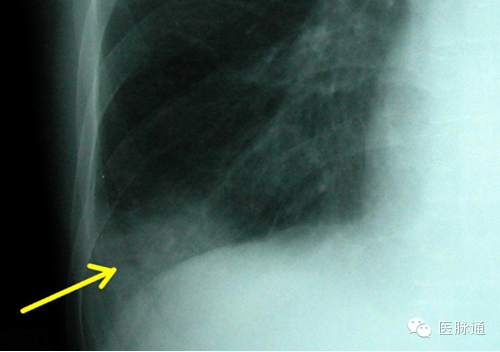

肺栓塞指肺动脉血流受阻。临床表现各异使得其难以准确诊断。虽然CT血管造影以及通气灌注扫描通常用于确诊肺动脉栓塞,但胸片可能存在多种表现。Westermark征指肺血管扩张且突然中断。Hampton驼峰为肺梗死和不张引起的周边肺组织的楔形实变(如图14箭头所示)。胸片还可见少量胸腔积液和膈肌抬高。值得注意的是,多数情况下肺栓塞患者胸片正常。

图14